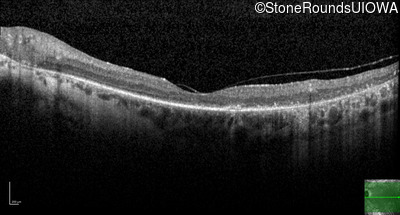

Optical Coherence Tomography - Left - 20/80 -2

Exemplar / OCT Stack